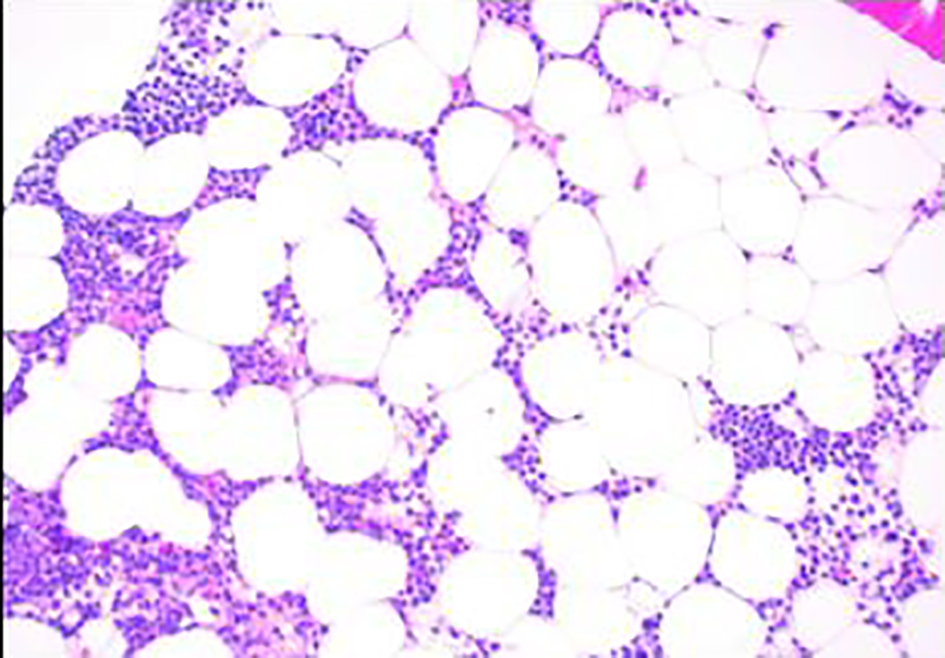

A 41-year-old, previously healthy, Hispanic man presented to the emergency room with complains of headache, difficulty in speech and generalized weakness. Physical exam revealed heart rate of 86/min, respiratory rate of 16/min, afebrile, and neurological exam was relevant for expressive aphasia and right-sided facial droop. Complete blood count showed pancytopenia with white blood cell (WBC) of 600/µL (4,500 - 11,000/µL), hemoglobin of 7.3 g/dL (13.2 - 17.5 g/dL) and platelet count of 14,000/µL (140,000 - 450,000/µL). Computed tomography of head showed multiple intracranial hemorrhage. Due to pancytopenia, bone marrow biopsy (BMB) (Figs. 1-4) was done which showed hypocellular marrow, and there was presence of cells resembling promyelocytes. Flow cytometry (Figs. 5 and 6) showed increased blasts (86.8% of total cells) and was positive for CD117, CD13, CD33 and CD64, negative for CD34 and HLA-Dr. Further, fluorescence in situ hybridization (FISH) study was done which was negative for t(15;17) and showed no other mutations. Karyotype was 46,XY, t(2;20)(q21;q13.1), del(14)(q24) (20). Next generation sequencing (NGS) was negative. Molecular testing using polymerase chain reaction (PCR) was not performed at that time. Diagnosis of AML was made. He was started on systemic chemotherapy with idarubicin and cytarabine. On chemotherapy day 15, bone marrow biopsy was repeated, which showed hypocellular bone marrow with no overt evidence of acute leukemia suggesting remission. However, after 1 year, he had abnormal outpatient complete blood count and so BMB was repeated, and he was found to have relapsed disease. BMB showed 31% blasts along with t(15;17) fusion. Karyotype was 46,XY, t(2;20)(q21;q13.1), del(14)(q24) (20). Diagnosis of APL was made this time. Because of the unexpected results, original AML sample was retested with FISH probe. FISH for t(15;17) was negative at initial presentation. A cryptic t(15;17) fusion was identified by FISH at relapse 1 year later, confirmed with molecular testing using PCR. The karyotype at initial presentation is identical to that at relapse which supports that this is AML acquiring t(15;17) at relapse. Patient was treated with ATRA and ATO, to which he responded very well.

![]() Click for large image | Figure 1. Bone marrow biopsy showing hypocellular marrow for age (× 100). |